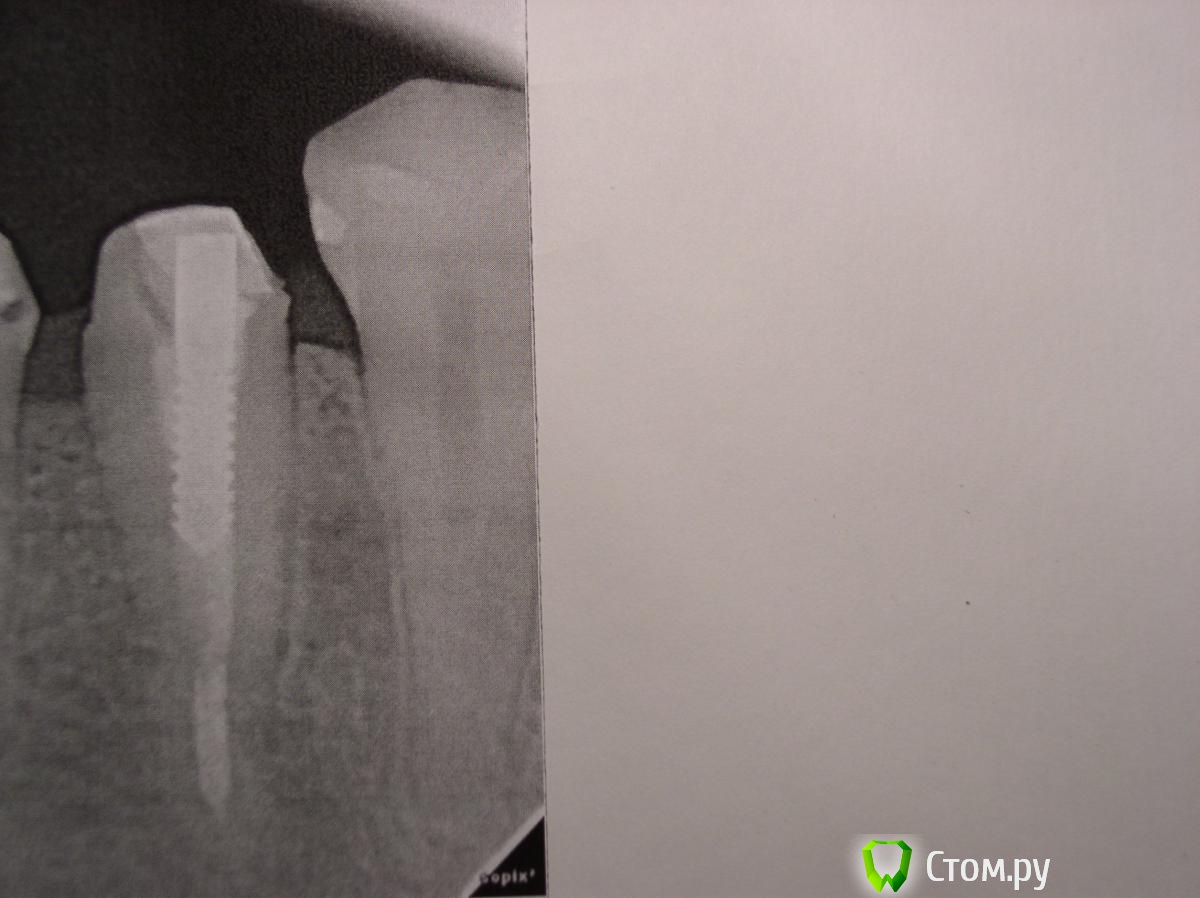

anaG2011 Опубликовано 20 ноября, 2014 Автор Поделиться Опубликовано 20 ноября, 2014 Тогда логичнее было выложить снимок без коронки.Добрый вечер, в приложении снимок пятерки без коронки.Можно ли поставить на пятерку половину от спаренной коронки и "наблюдать" за ним пока не забеспокоит или необходимо перелечить его уже сейчас. Ссылка на комментарий

anaG2011 Опубликовано 24 ноября, 2014 Автор Поделиться Опубликовано 24 ноября, 2014 Добрый вечер, в шестерке стоит временная пломба. Каналы перелечены. Ортопед предлагает в 6-ку поставить титановый штифт, а у пятерки заменить пломбу (штифт оставить, каналы не трогать).Поставить опять спаренную м/к коронку. http://s017.radikal.ru/i406/1411/89/fb325c36299a.jpg- прицельный рентген. снимок 5 и 6 http://s017.radikal.ru/i433/1411/fb/2089cd590e34.jpg- прицельный снимок 5 и 6 на визиографе Уважаемые доктора, посмотрите, пожалуйста, снимки, какое Ваше мнение? Ссылка на комментарий